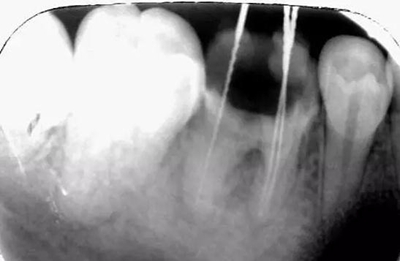

根充后:

沖洗后封閉氫氧化鈣一周后MTA修補:

MTA:有點太貴啦,這個病號是個在校的大學(xué)生統(tǒng)統(tǒng)的費用700,專門為他訂購的材料,我真的盡力啦。

修補后:

沒有顯微鏡和MTA輸送器做的有點不精致,幸好還有個放大鏡要不更累啦。